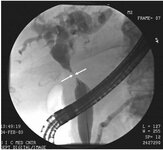

CPRE de colangiocarcinoma hilar: tumor de Klatskin com estenose da bifurcação do ducto (setas)

Do acervo de Dr. Joseph Espat; usado com permissão